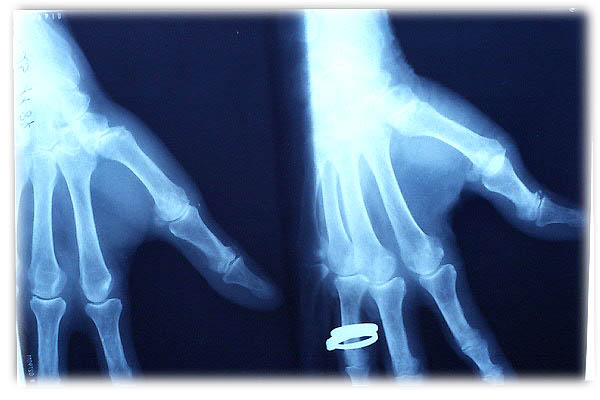

ACT Alteraciones degenerativas en muñeca.

Artritis psoriásica y falange bífida.

Artritis psoriásica.

Falange distal de dedo 1º de mano, bífida.